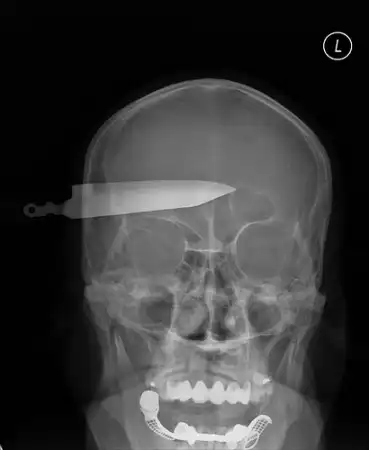

Миф об отверстиях в мозге

Некоторые люди считают, что механические повреждения мозга (чему причиной может быть черепно-мозговая травма, причиненная ножом, штыком, железным прутом) приводят к образованию отверстий, пустот в мозге. Это не так. Ткани мозга, как уже говорилось, подобны желе, поэтому никаких дыр не образуется, можно говорить просто о временно или перманентно недееспособных поврежденных областях. Все эти "дыры" и "пустоты" - миф, поскольку ткани мозга мгновенно заполняют любую образовавшуюся прореху.